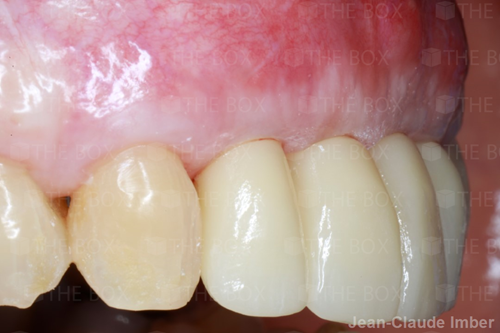

A new case was made public by Jean-Claude Imber check it out here.